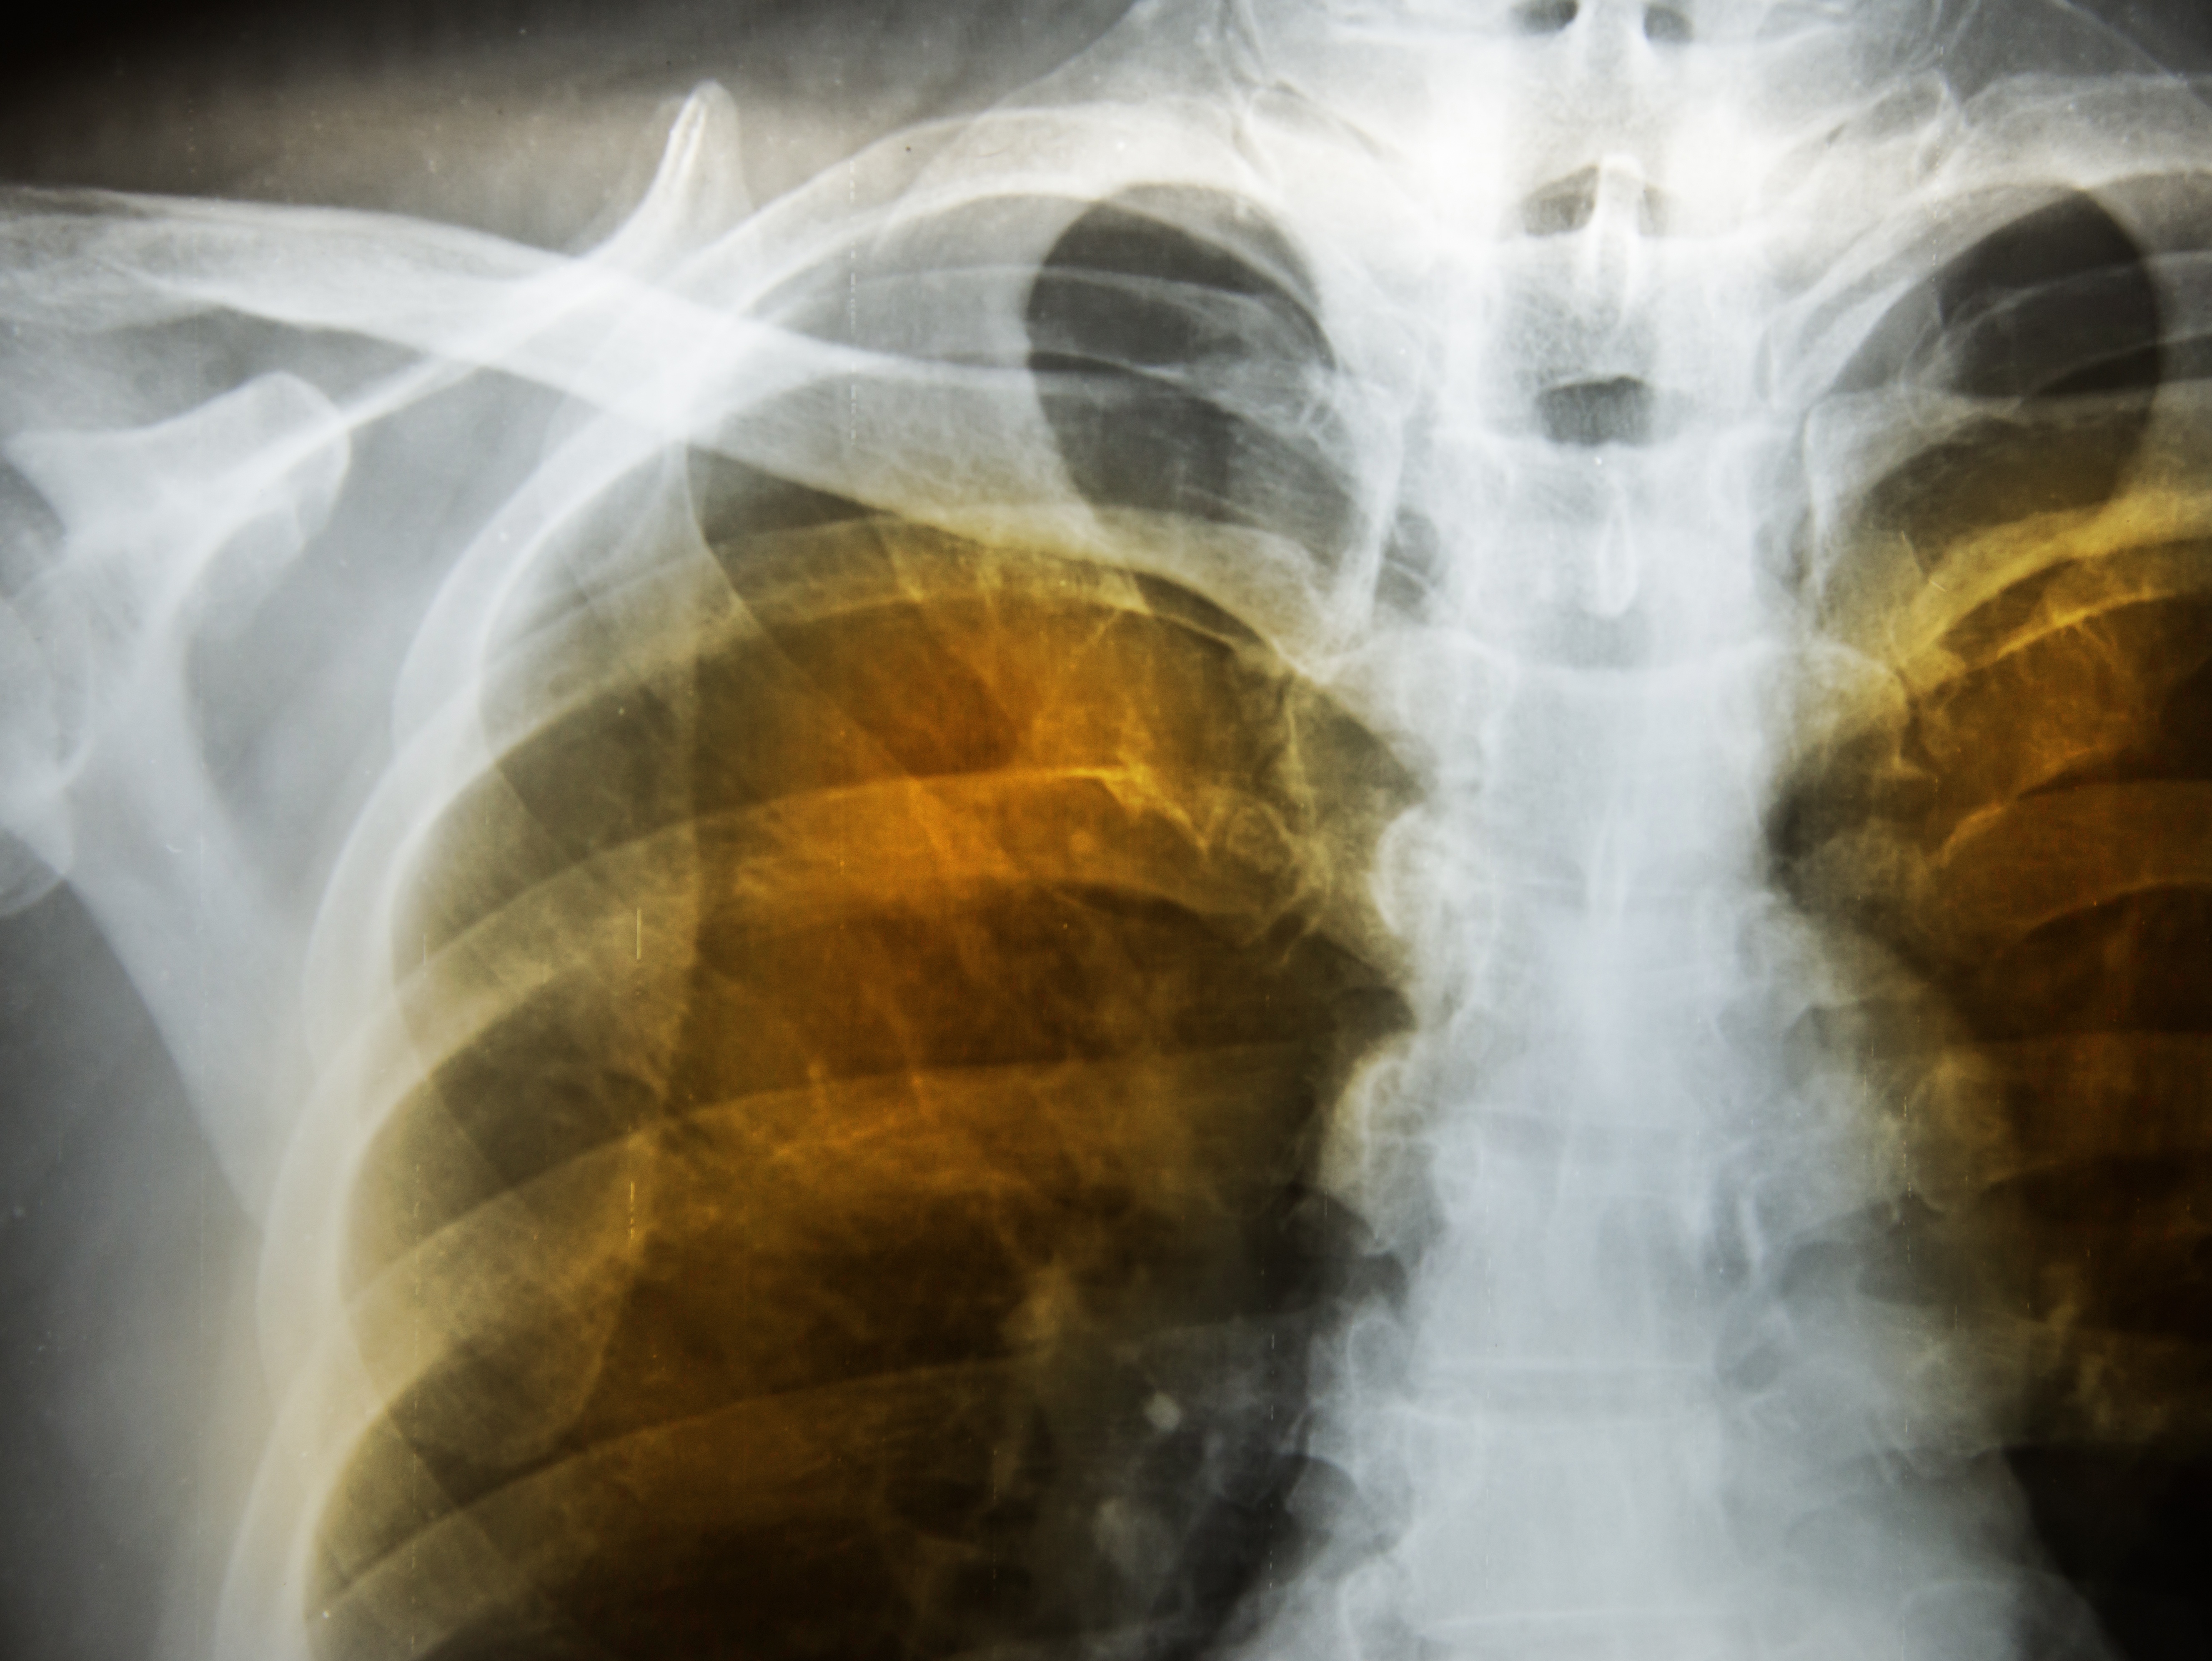

Chronic Obstructive Pulmonary Disease (COPD) is an umbrella term used to describe progressive lung diseases including chronic bronchitis, emphysema, some forms of bronchiectasis and refractory asthma. COPD is the third leading cause of death in the United States and is believed to claim the lives of more than 120,000 adults every year.

The dilemma is that patients must be well enough to tolerate major surgery, but advanced COPD patients may not fit this bill. Even so, surgical intervention can be a very good option for some patients. Surgical treatments for COPD can take one of three forms; Lung Volume Reduction Surgery (LVRS), lung transplantation or bullectomy.